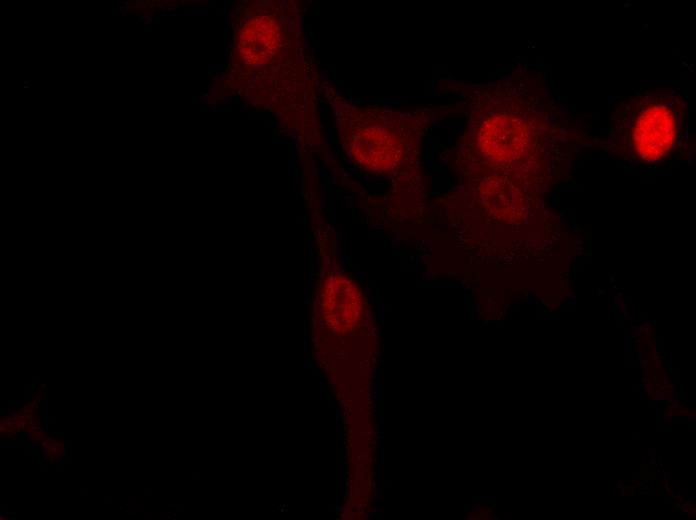

BRCA1M1138